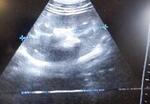

超音波検査